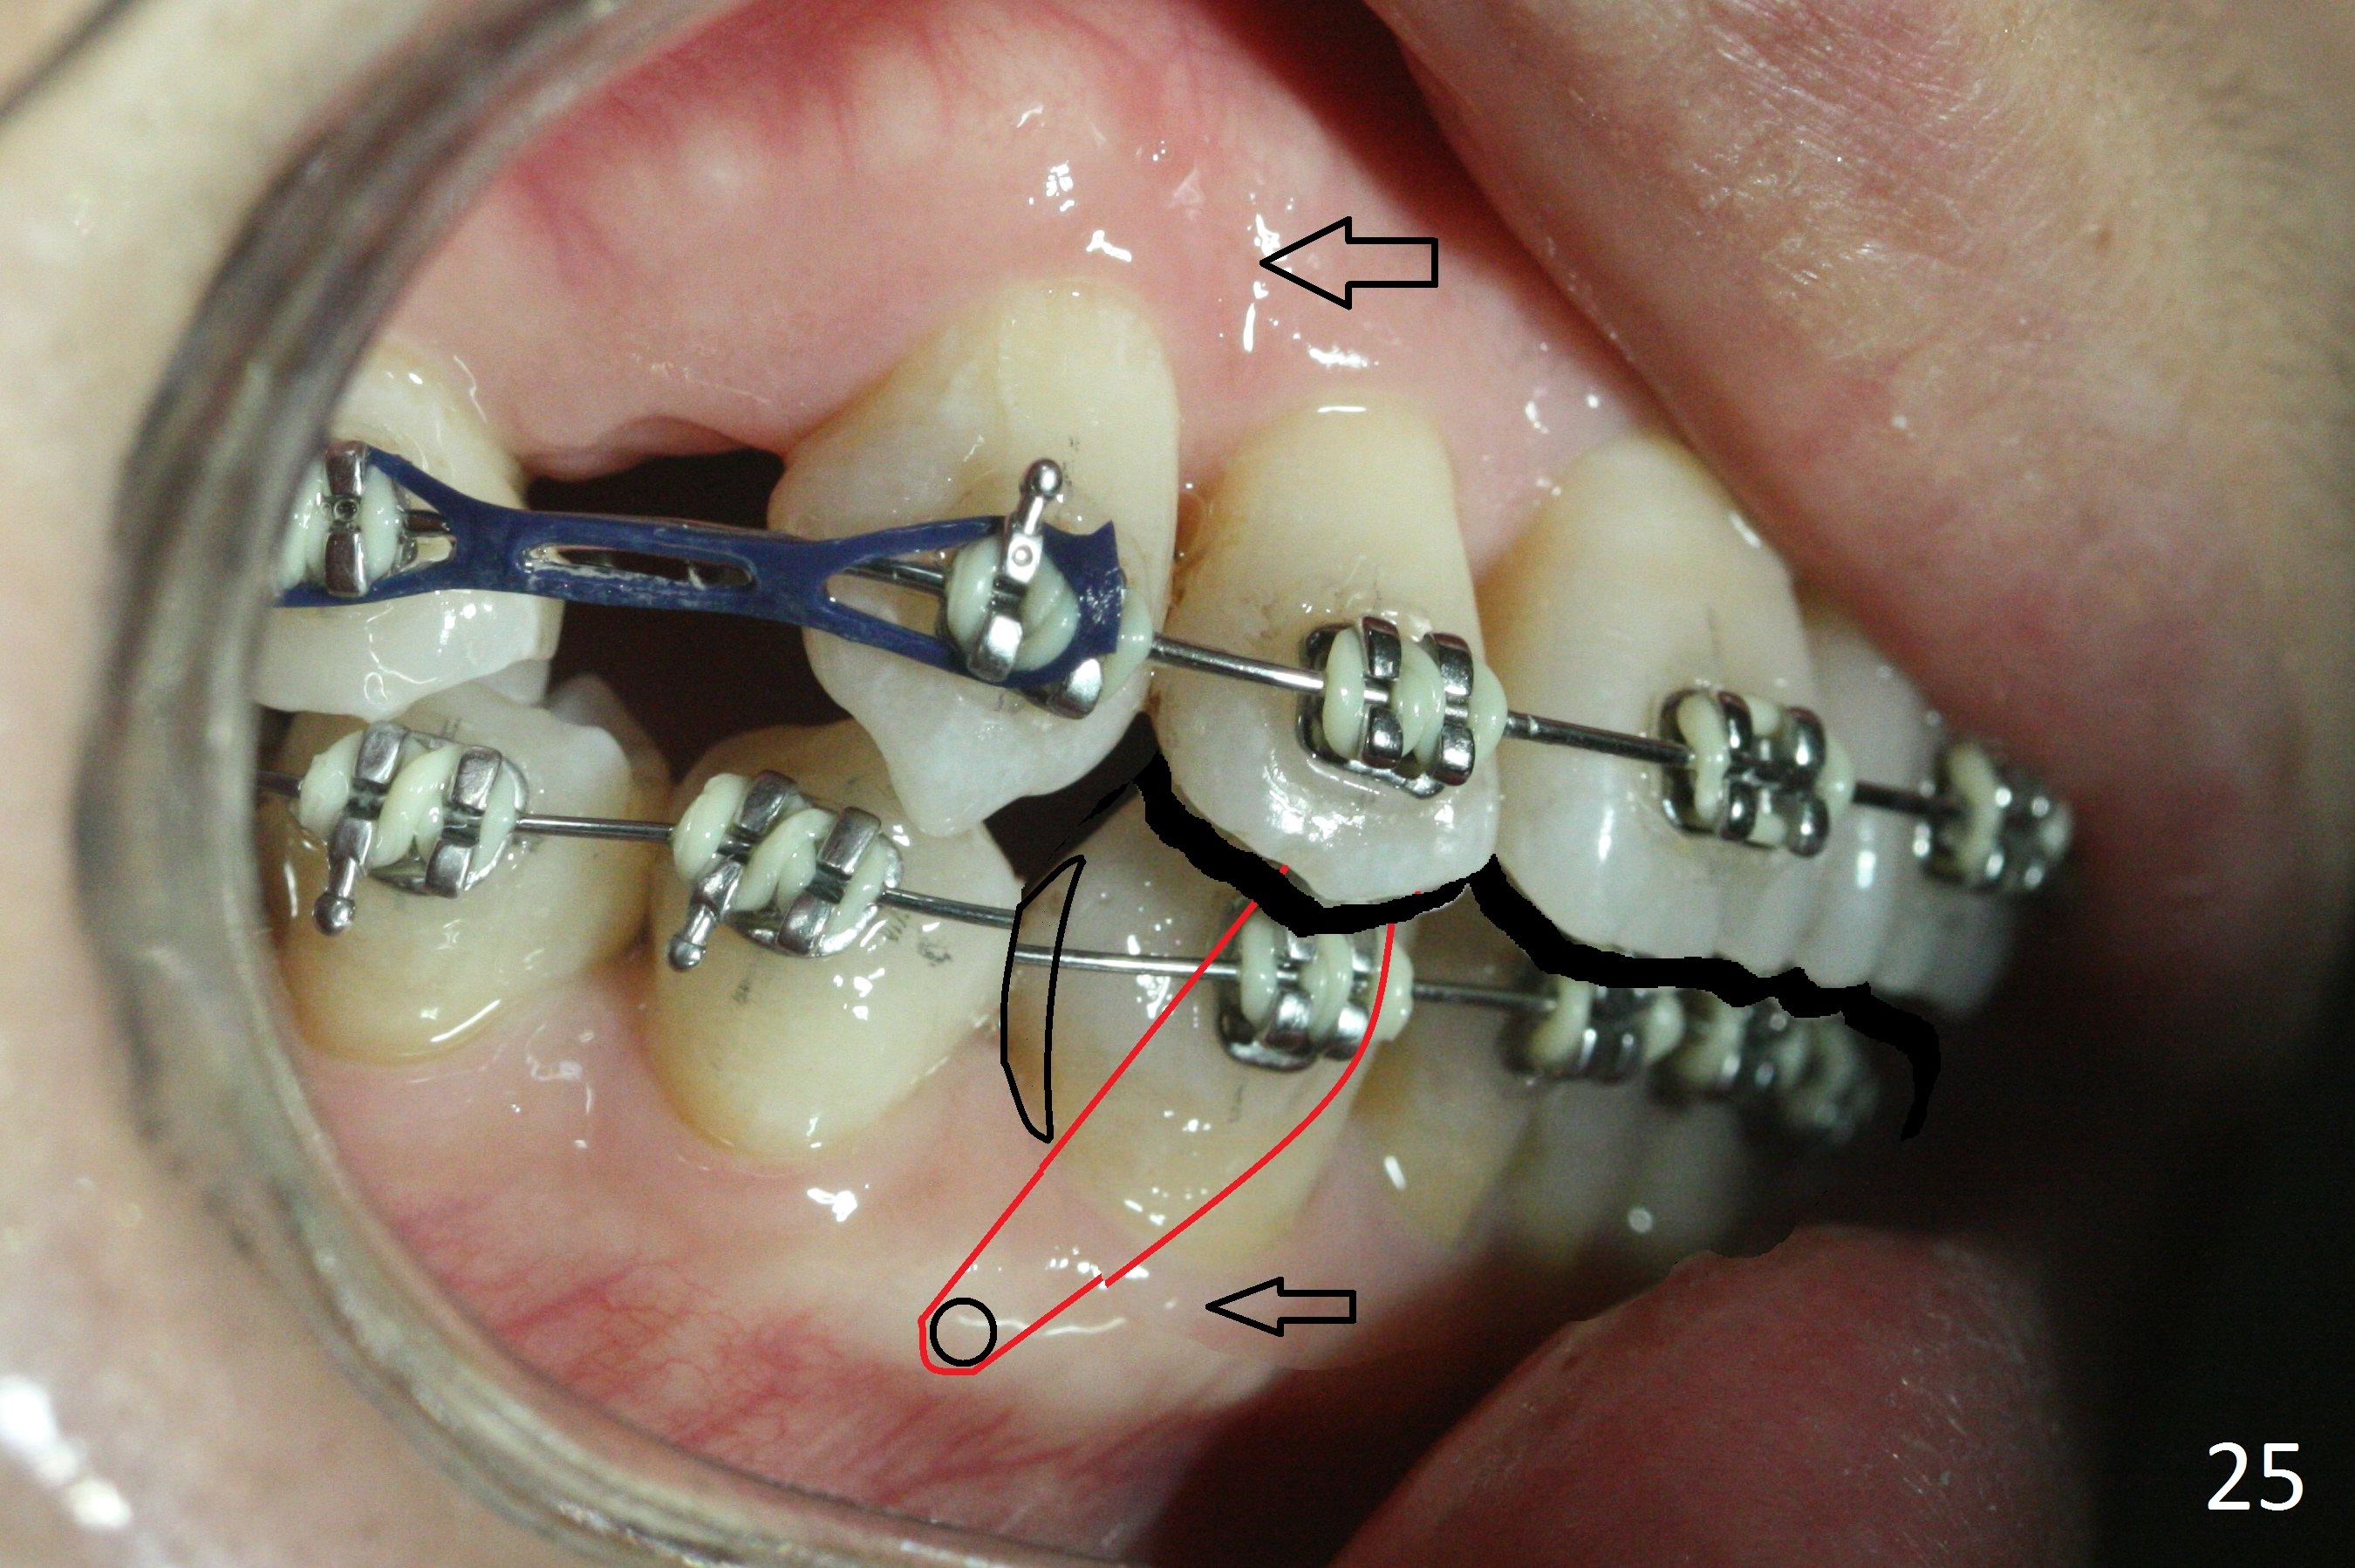

The rotation of the upper canines is not corrected much in the next 3.5 months (Fig.21, as compared to Fig.18). Distalization of the upper right canine is implemented by power chain, but this is not sufficient because of the anterior deep bite. Note the tension of 18 niti wire between LR 3 and 4 (^). Mini implants are going to be placed mesial or distal to L3s (Fig.22,23 circles) to intrude the lower anterior teeth with elastic or power chain (Fig.23 red line, 24 black area). The upper anteriors will have space to be distalized (Fig.24 arrow). If necessary, proximal reduction will be accomplished at LR3 (extra wide, Fig.25 black outline) for further overjet correction (arrows).